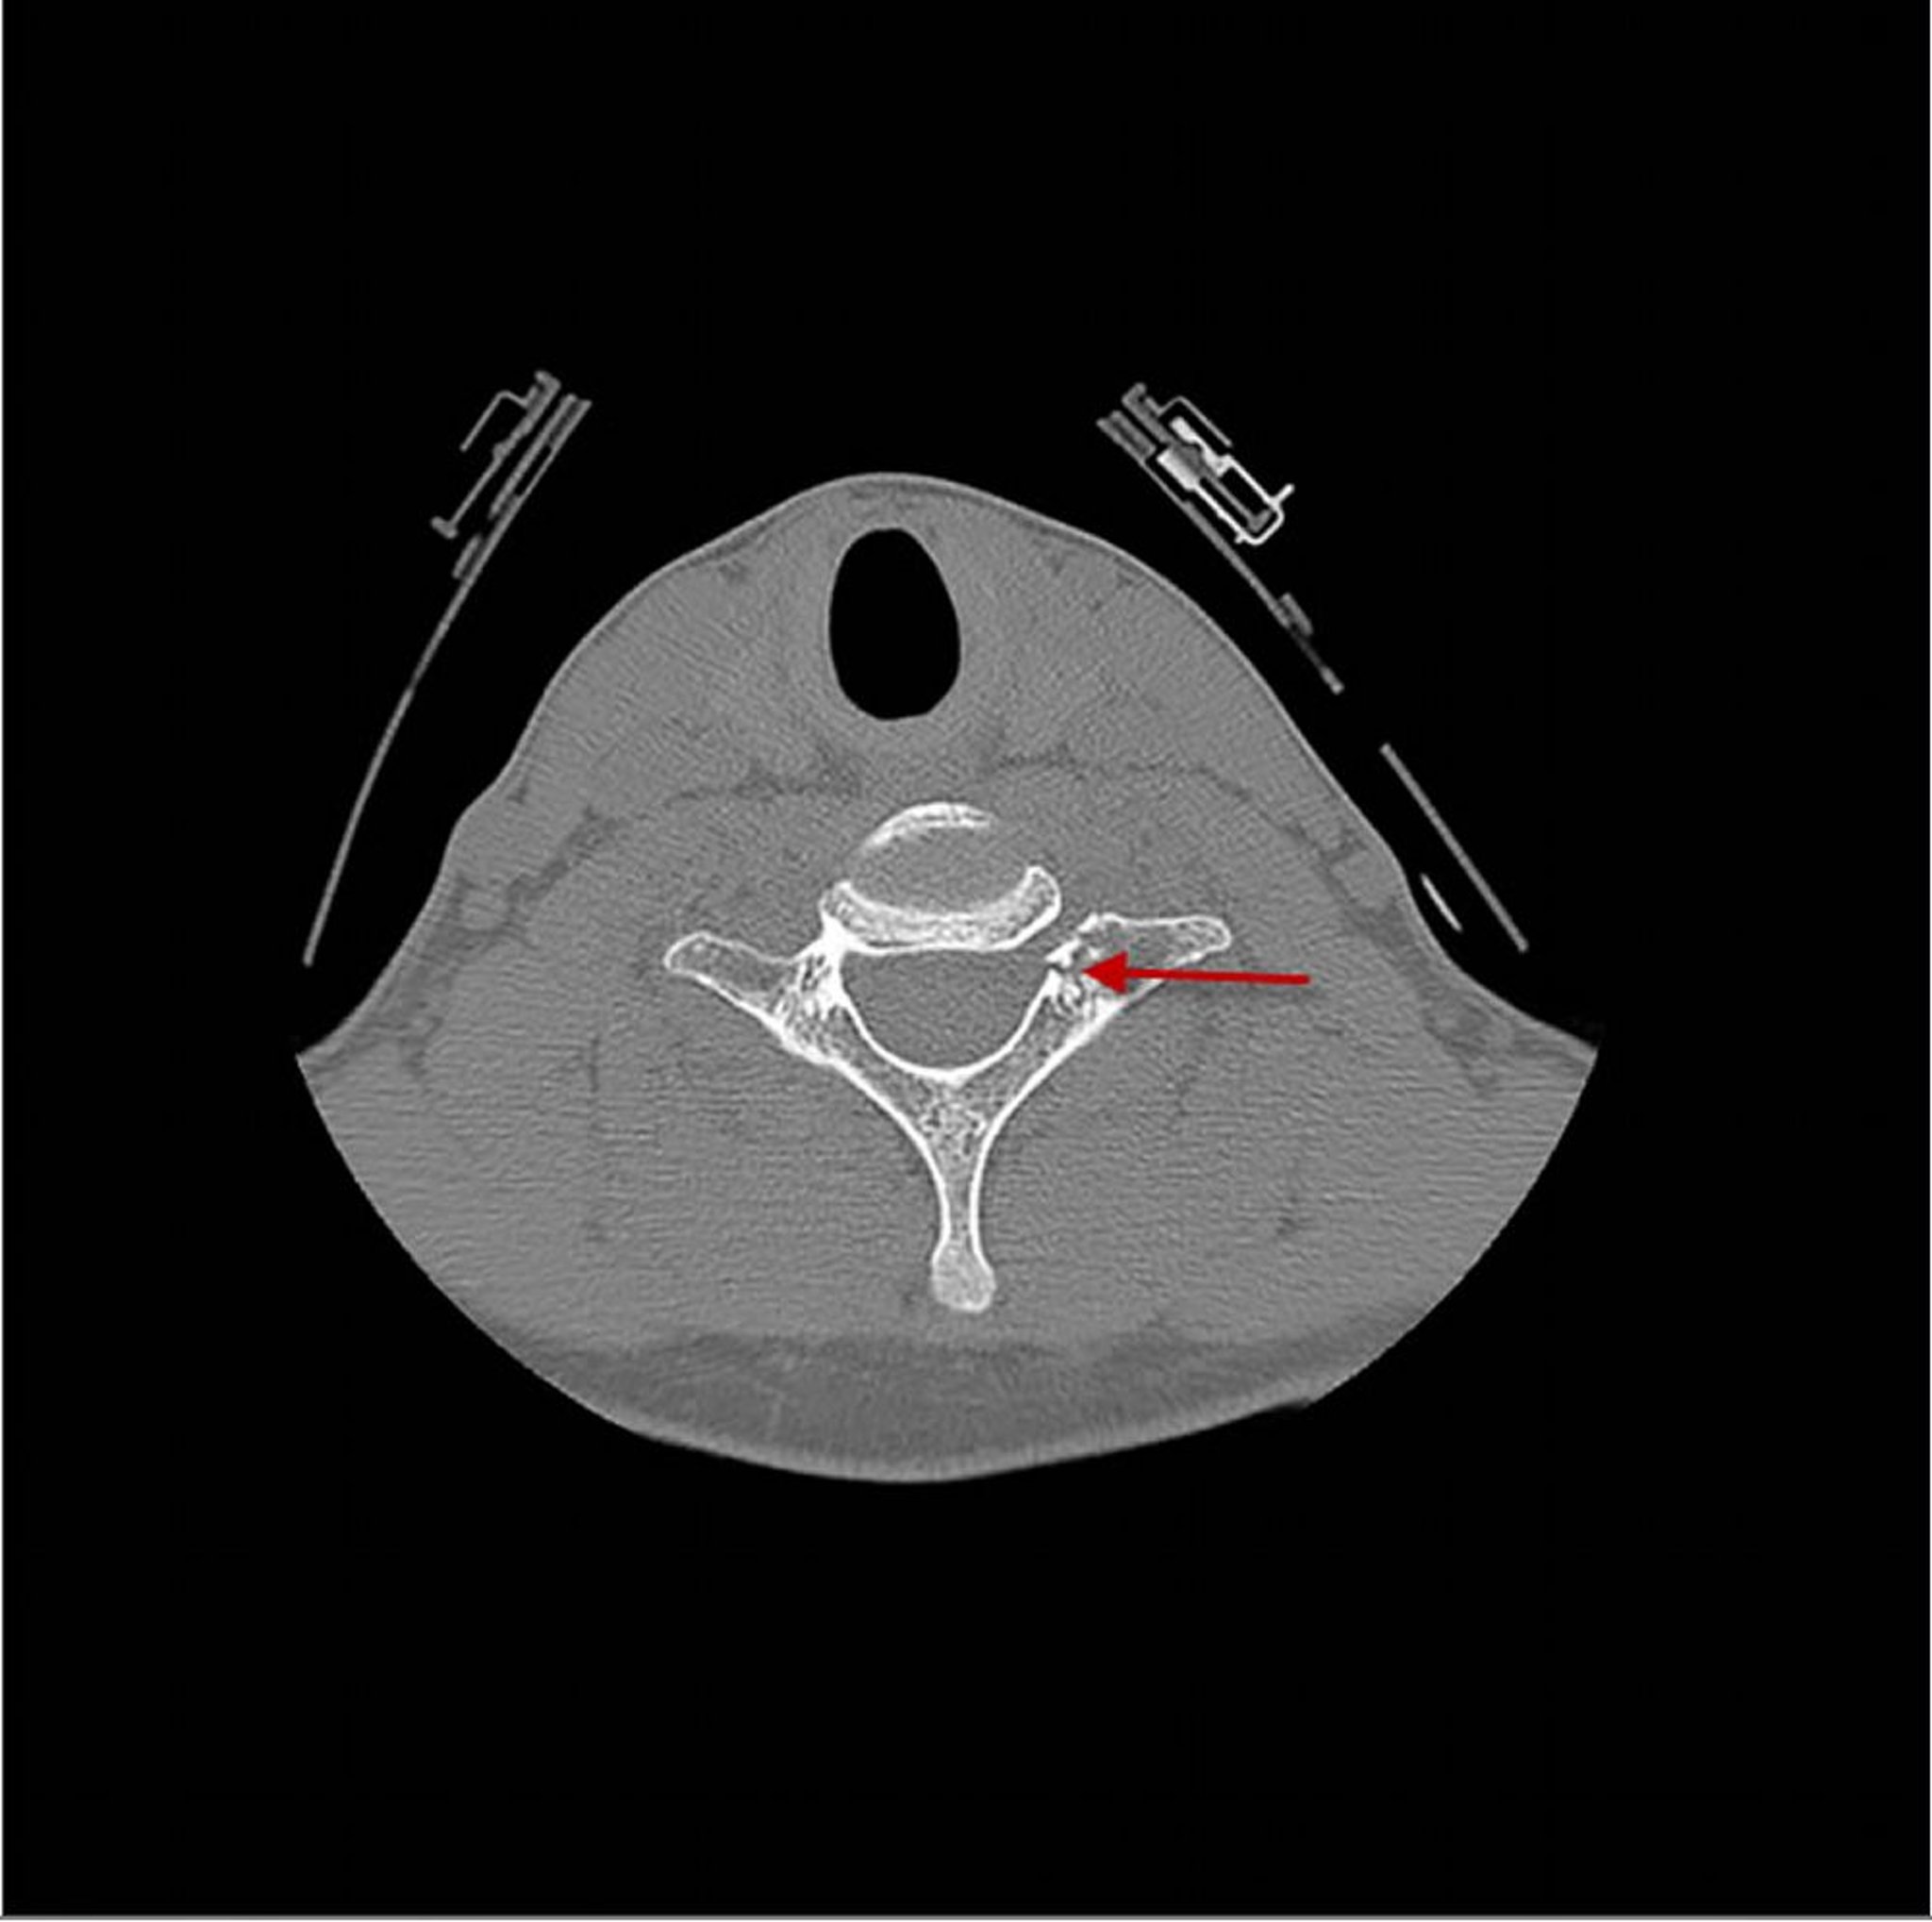

This CT shows a fracture (arrow) through the 7th cervical vertebra just posterior to the vertebral body.